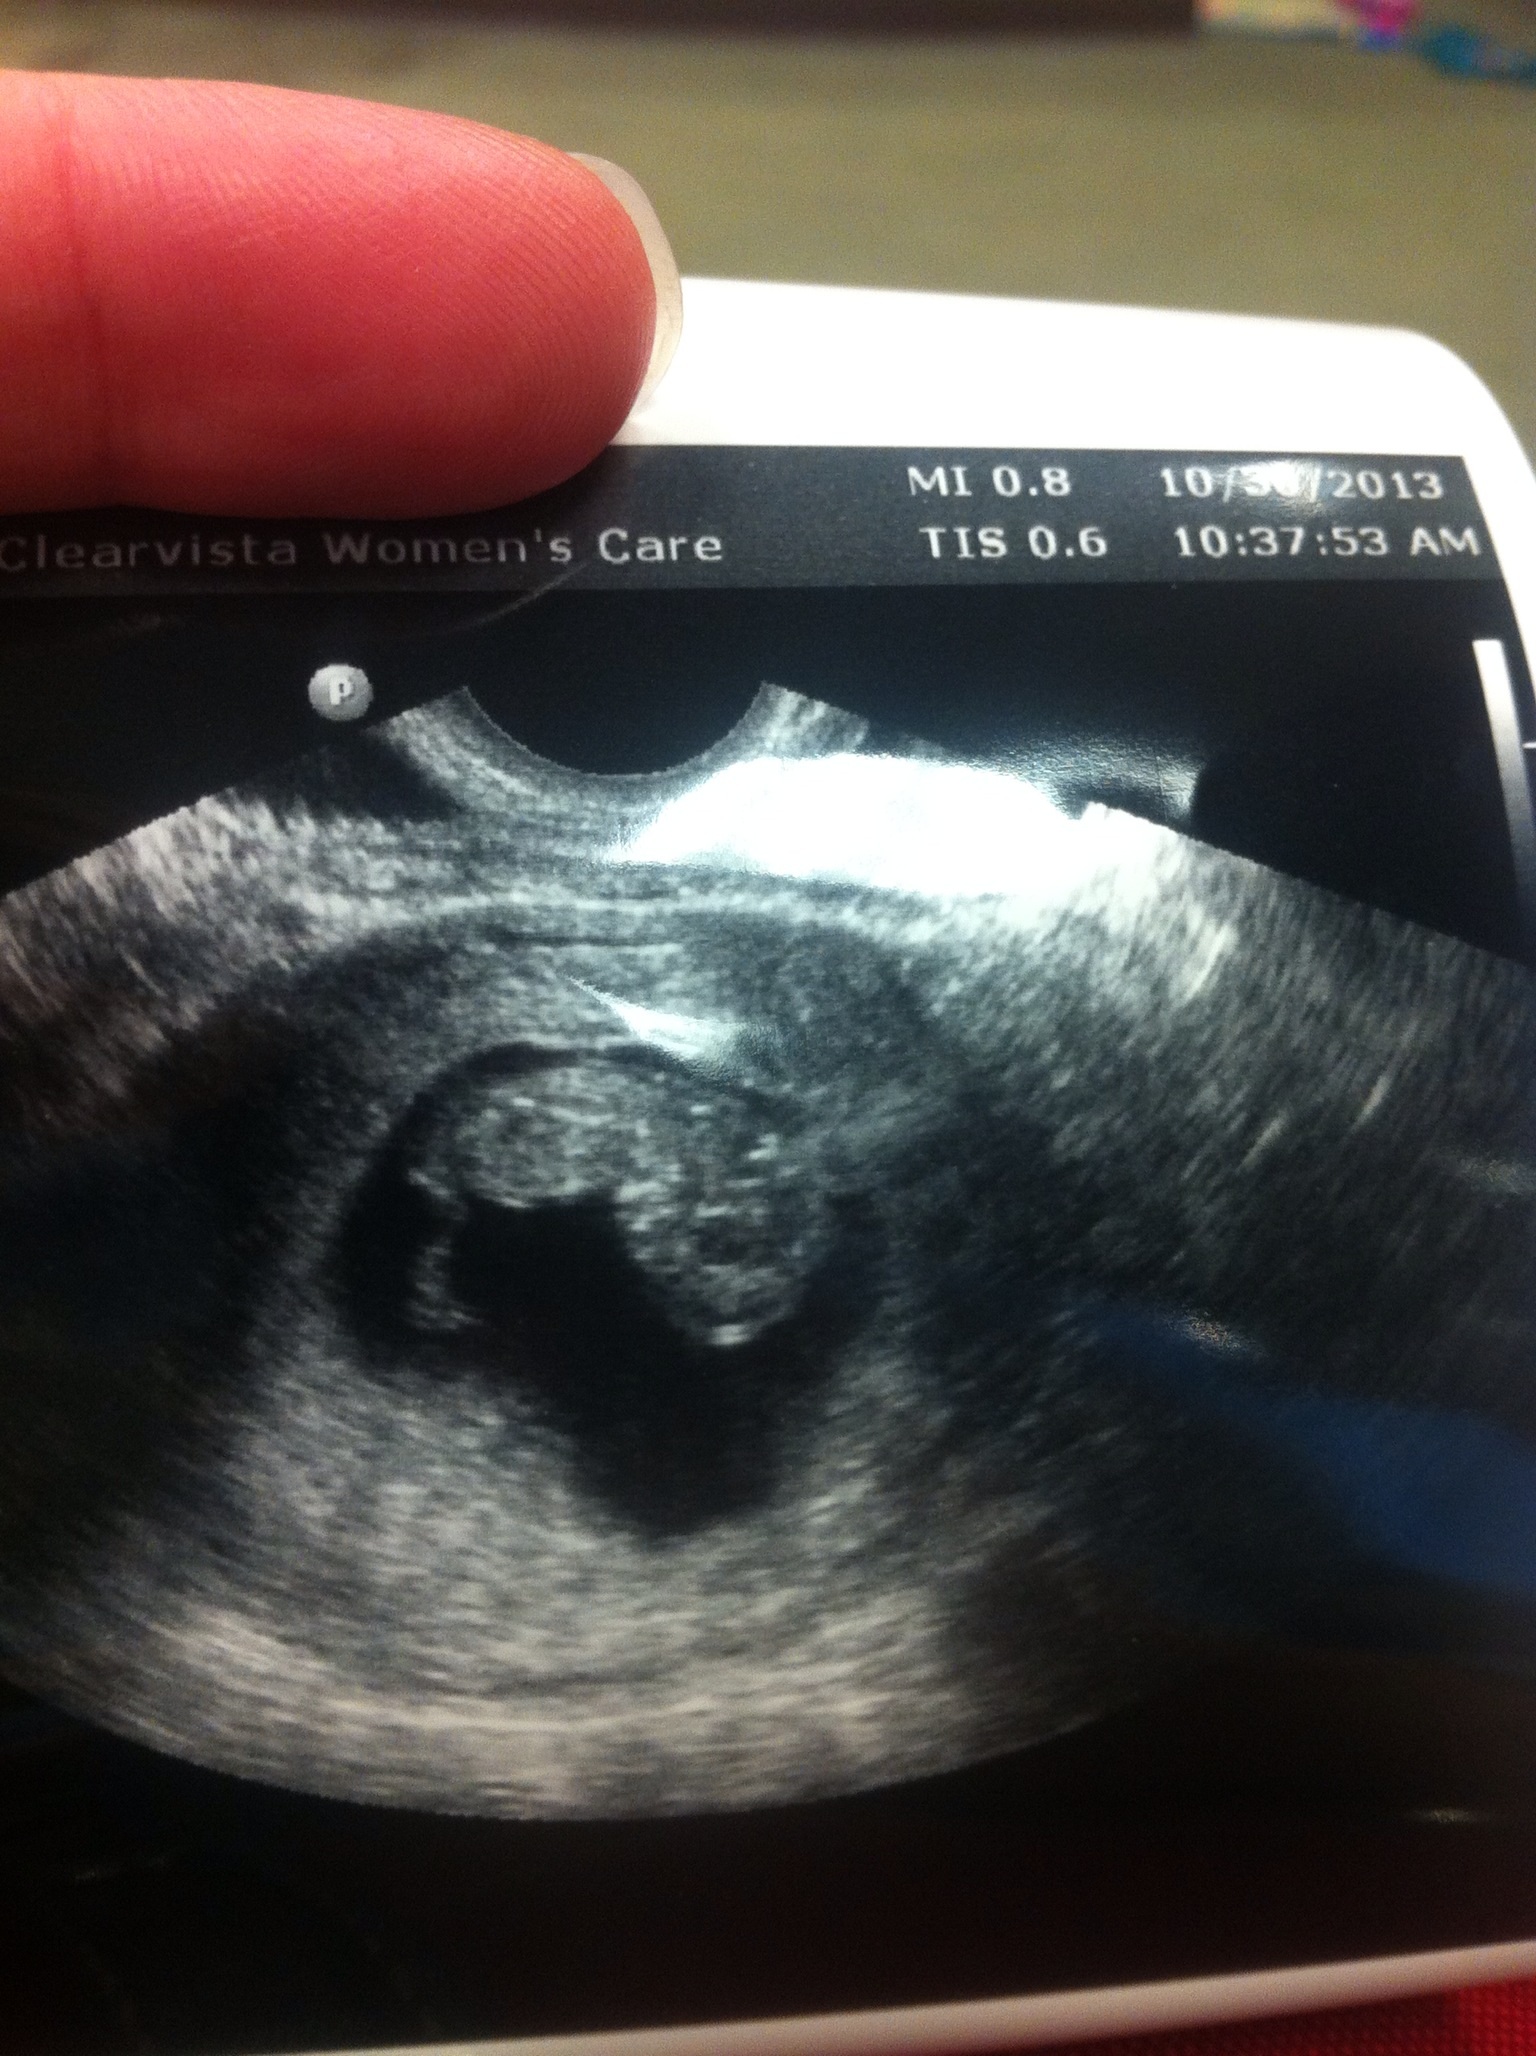

I have my 3rd u/s today at 10:30. I should be 10w 2d which is about right where I was when I found out our baby had stopped growing (at 8w) last time. I am pretty nervous. I'm desperately hoping for a healthy baby with a beautiful heartbeat. I'd appreciate any thoughts you can spare!

Baby is ok!! It measured 10w 1d with a h/r of 166. Still a long way to go, but I'm very relieved to have passed this point. I am so sincerely grateful for all the support on here. Not many people in RL know. I really do appreciate it.